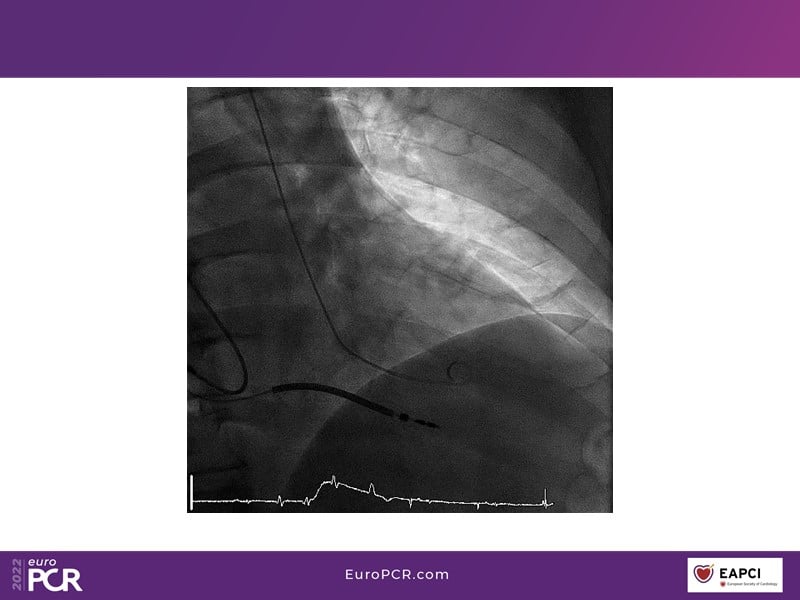

Tailored support for complex PCI and AMI with percutaneous mechanical circulatory support

Watch this EuroPCR 2022 session, in which Javier Escaned, Florim Cuculi, and Norman Mangner present different cases, to learn how standard operating procedures including mechanical circulatory support improve outcomes in patients with complex coronary lesions, discuss new strategies to overcome ischemic reperfusion lesions using percutaneous mechanical circulatory support, and understand the benefits of mechanical circulatory support in AMI patients.